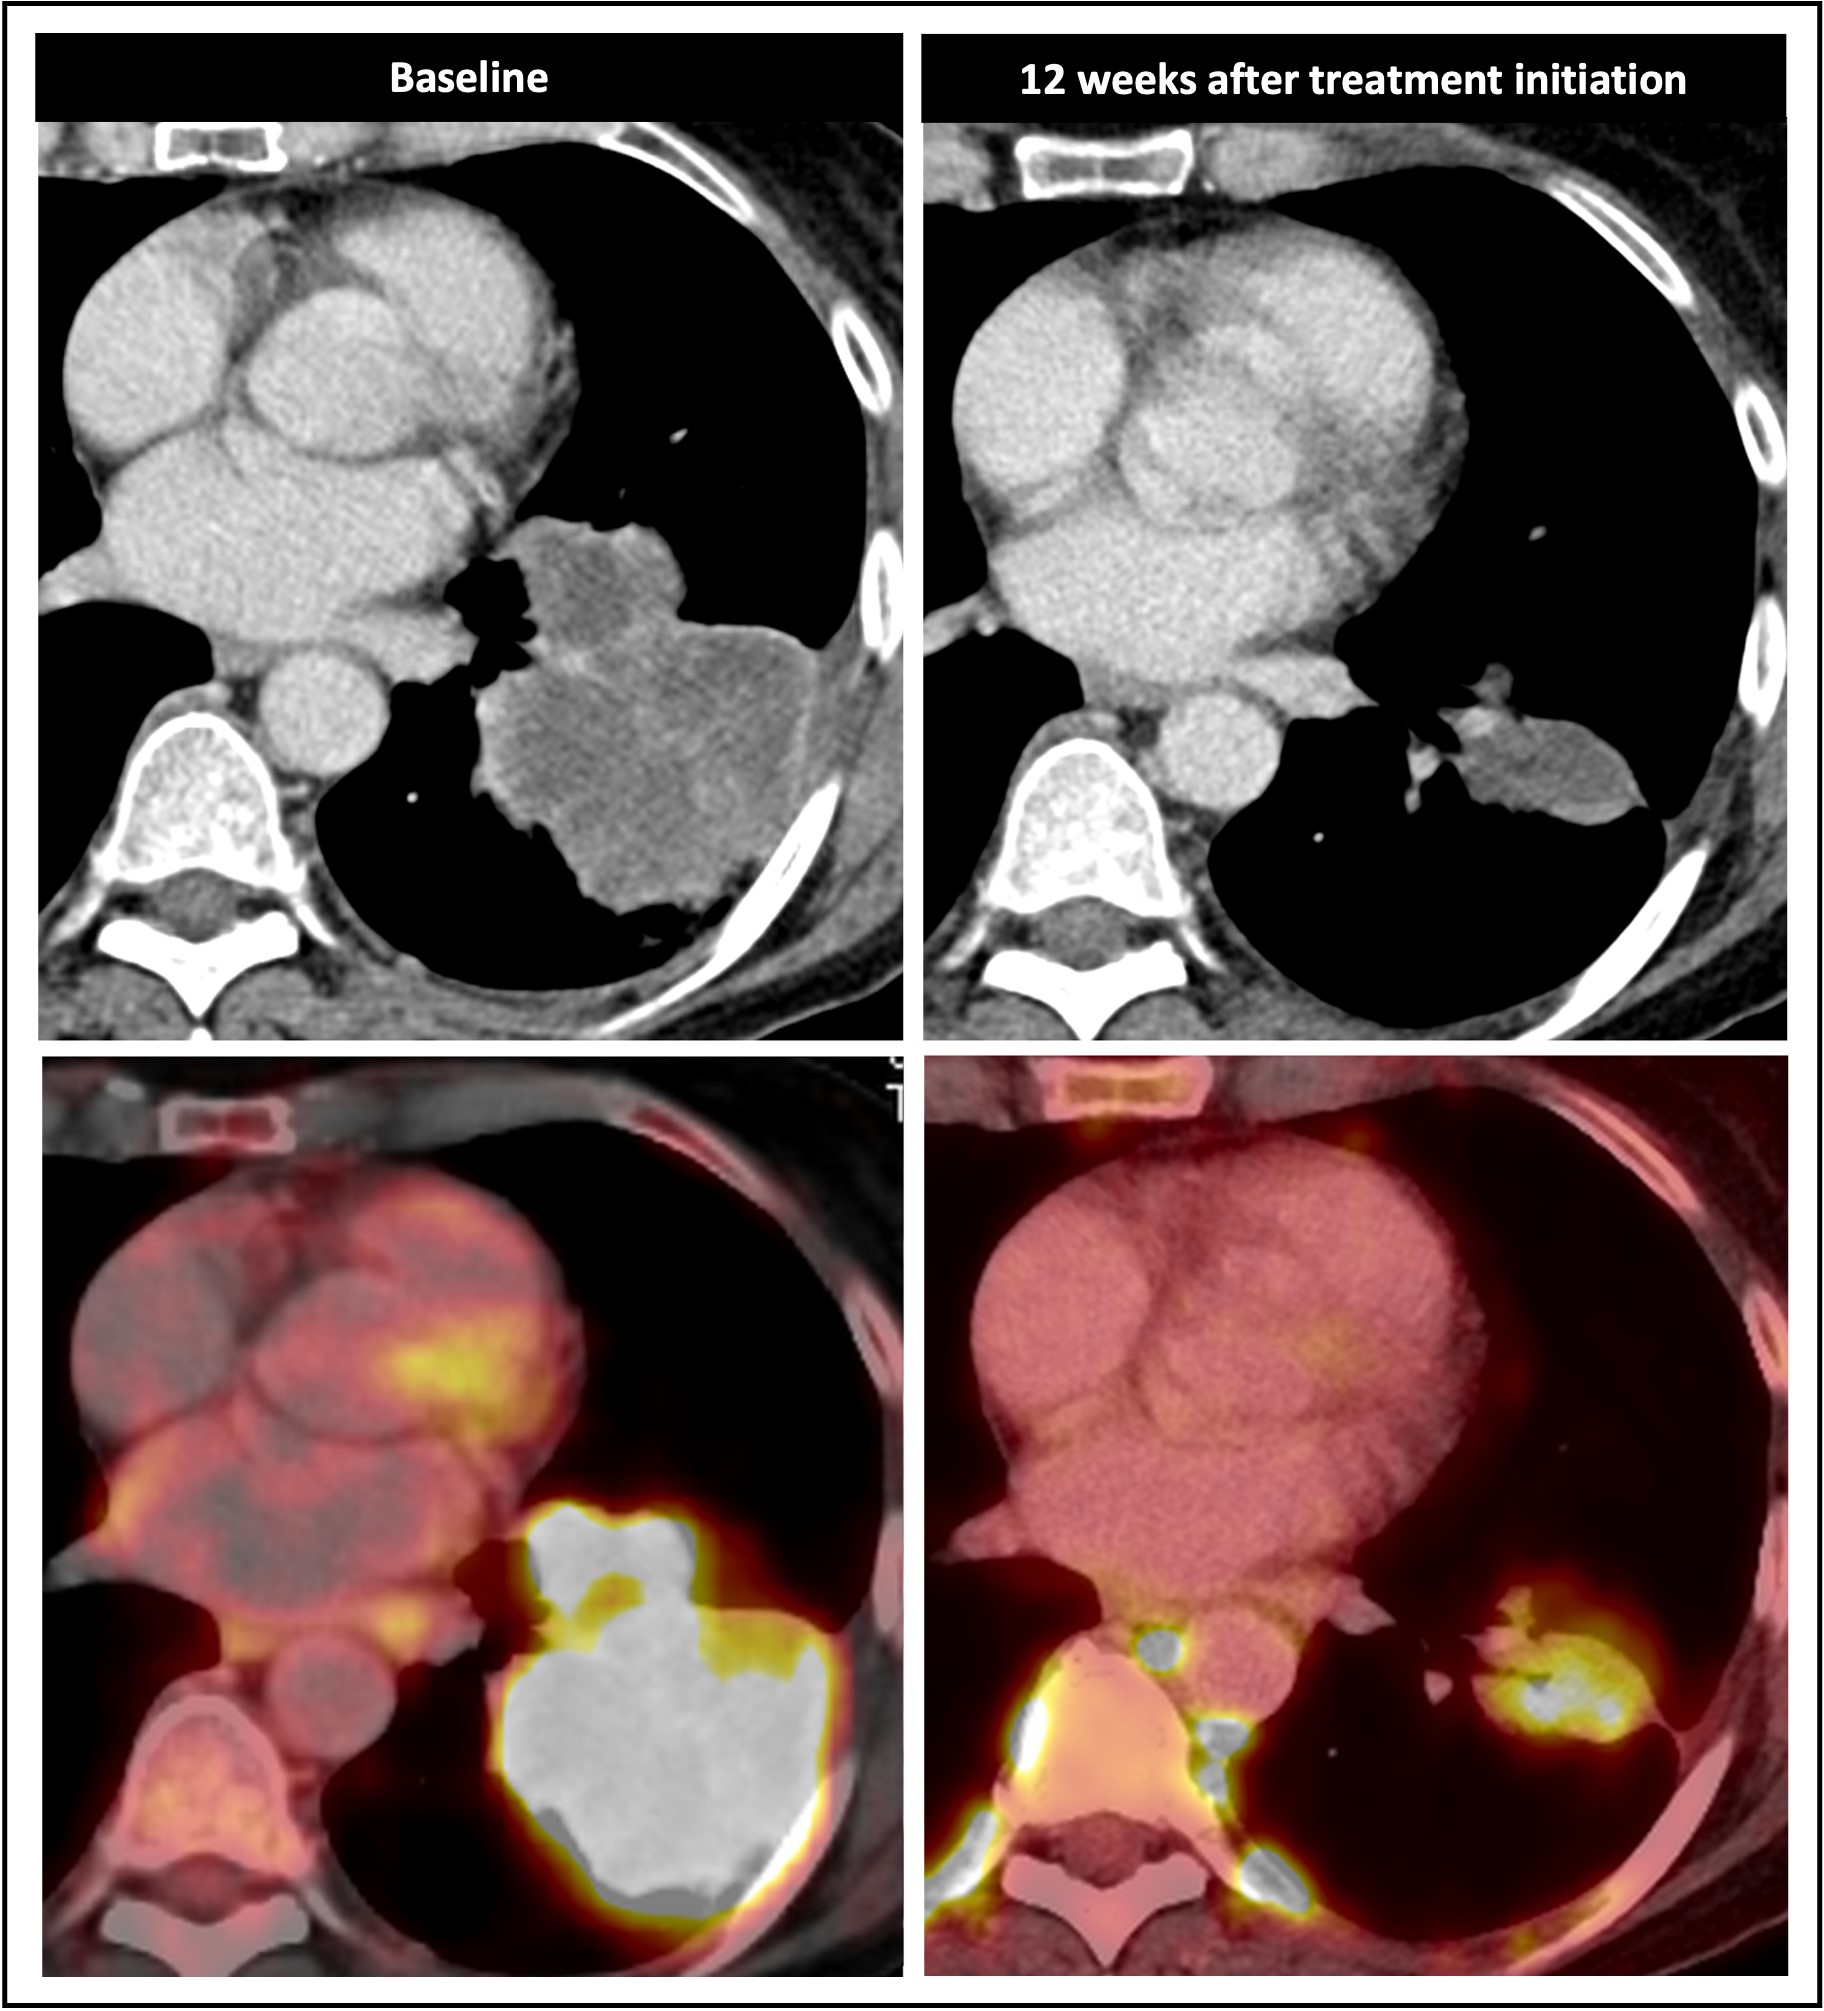

Maximum-intensity projection F-18 FDG-PET (left) and Ga-68 FAPI-PET (right) images of synchronous ILC. (A) A 42-year-old patient with multicentric primary lesions (encircled), regional (solid arrows), and distant inferior jugular lymph node (dashed arrows) seen on F-18 FDG-PET and subsequently confirmed on Ga-68 FAPI-PET, which also revealed additional malignant foci aligned with MRI. Some lesions exhibited high activity retention on Ga-68 FAPI-PET. (B) A 53-year-old patient showing no significant uptake on F-18 FDG-PET but synchronous bilateral lesions (arrows) on Ga-68 FAPI-PET, which also identified pathologic lymph nodes (encircled), resulting in upstaging. Image courtesy of the Journal of Nuclear Medicine.